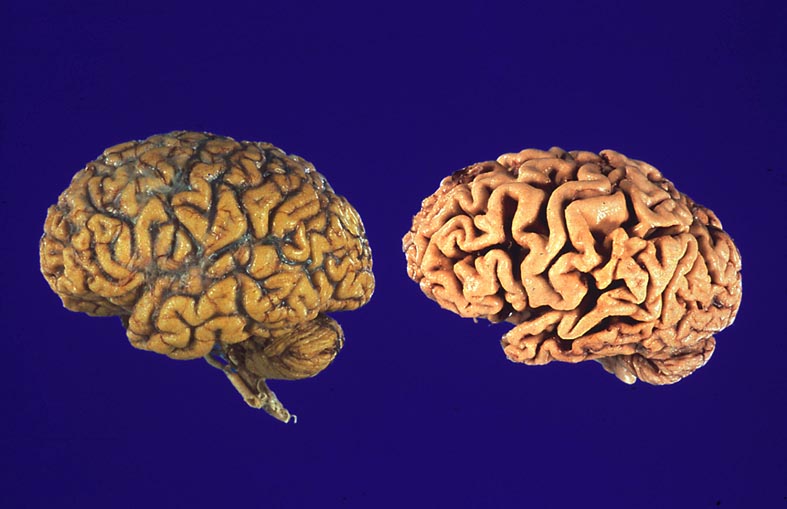

Gehirne von Alzheimer Patienten sind makroskopisch durch eine kortikale Atrophie (vor allem temporo-parietal) charakterisiert. Weiter findet sich meist eine deutliche Atrophie von Hippocampi und Mandelkernen. Diese geht einher mit einem Hydrocephalus internus (e vacuo), wobei vor allem die Temporalhörner der Seitenventrikel betroffen sind.